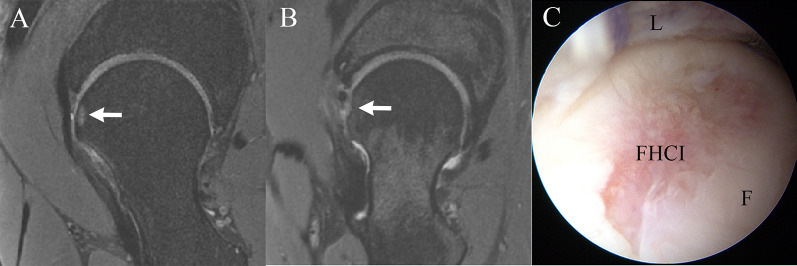

Background: Postoperative femoral head cartilage injury (FHCI) is a rare condition that can be observed in a certain proportion of patients undergoing hip arthroscopy. However, the prevalence and associated factors of FHCI, and the effect of this condition on clinical outcomes still remain unknown.

Patients and methods: Consecutive patients who were diagnosed with femoroacetabular impingement syndrome (FAIS) and labral tear and underwent hip arthroscopic treatment in our institute between July 2020 and July 2021 were retrospectively evaluated. Supine anteroposterior hip radiographs, cross-table lateral radiographs, magnetic resonance imaging (MRI), and computed tomography (CT) were obtained preoperatively. Postoperative MRI, at least 6 months after arthroscopy, was performed. Postoperative FHCI was evaluated by two surgeons through MRI. Preoperative patient-reported outcomes (PROs) including visual analog scale (VAS) for pain, and modified Harris Hip Score (mHHS) before surgery and at final followup were obtained.

Results: A total of 196 patients were included. Postoperative FHCI was identified in 21 (10.7%) patients. The intraobserver reliability of the observer A and B for detecting postoperative FHCI using 3.0-T MRI was high (k = 0.929, and k = 0.947, respectively). The interobserver reliability between the two observers for detecting FHCI using 3.0-T MRI was high (k = 0.919). There was no significant difference in preoperative and postoperative mHHS, VAS, and percentage of patients who surpassed minimal clinically important difference (MCID) and achieved patient acceptable symptom state (PASS) between patients with and without postoperative FHCI (P > 0.05).

Conclusion: Although postoperative FHCI was observed in 10.7% of patients, which was associated with larger labrum, this condition did not result in inferior clinical outcomes. Level of evidence IV, retrospective case series. Trial registration The Chinese Clinical Trial Registry approved the registration (ChiCTR2200061166). The date of registration is 2022-06-15.